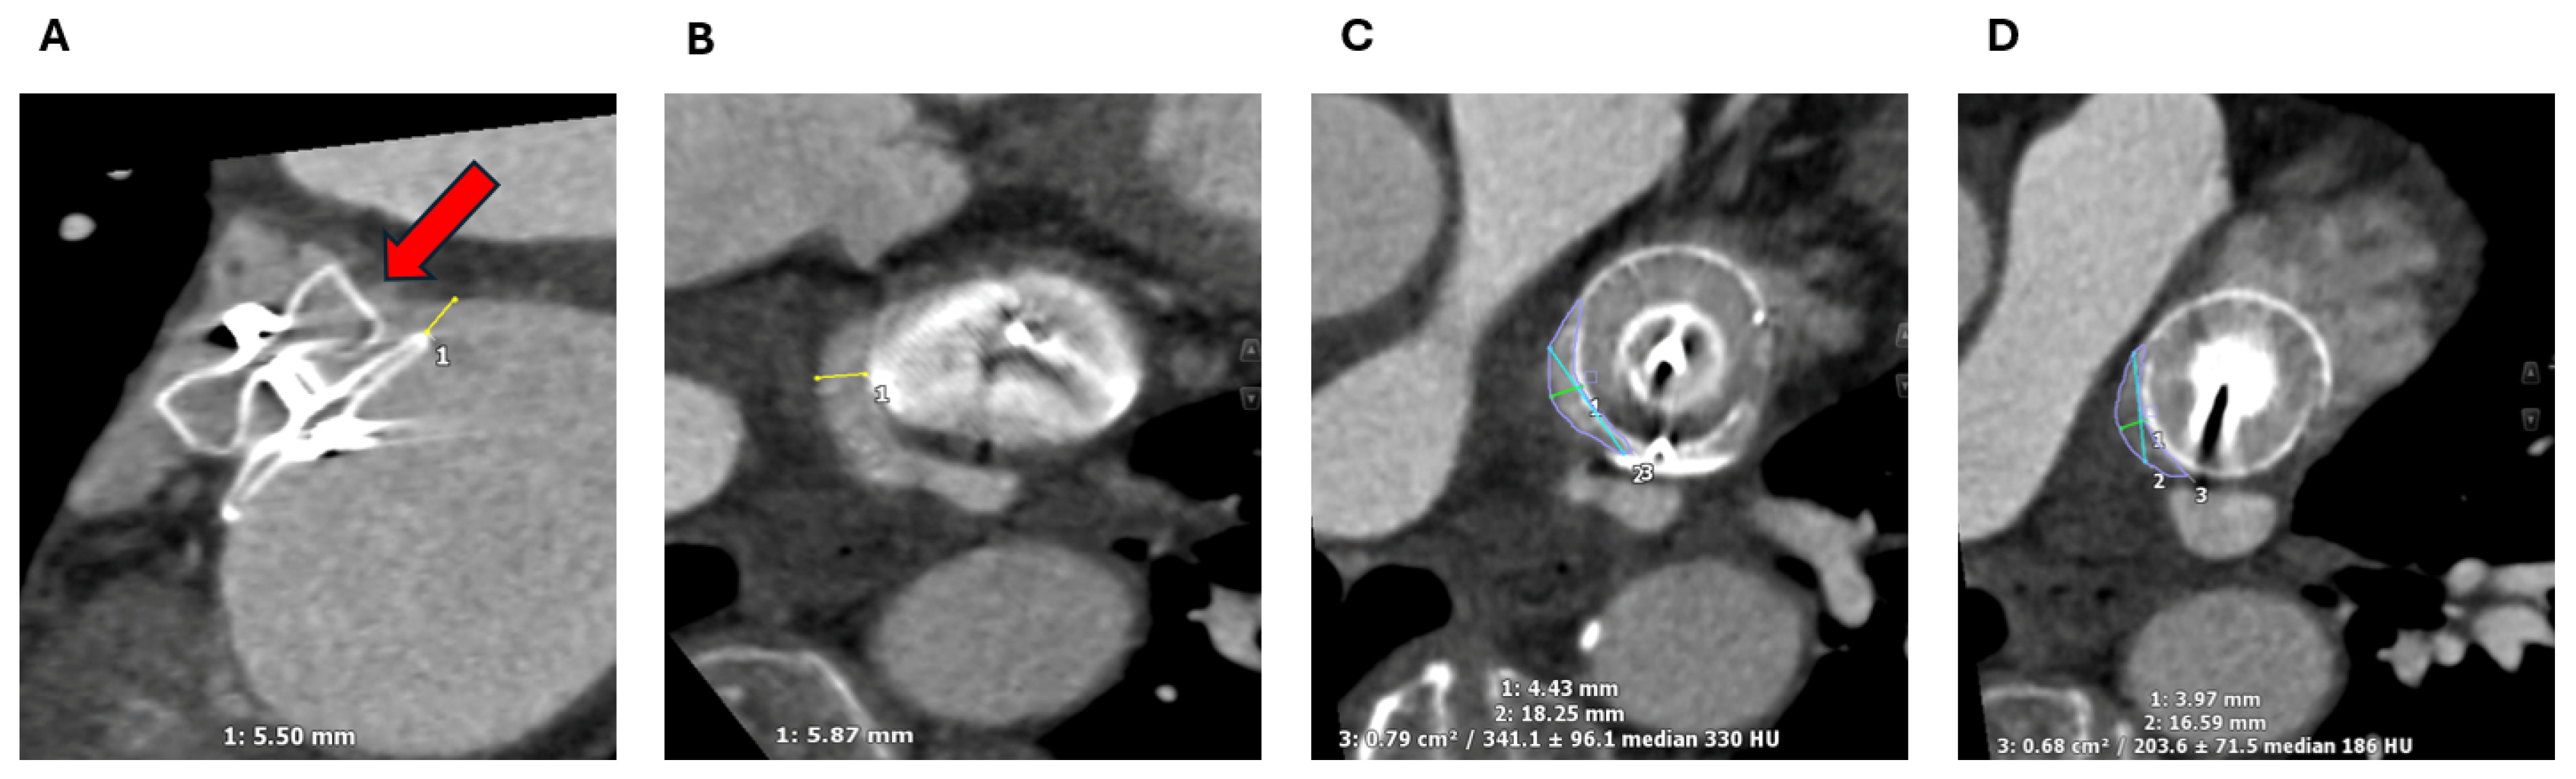

2.1. Cardiac CT

2.1.2. LAA Measurements

2.1.3. Assessment of the Inter-Atrial Septum

2.1.4. Other Anatomical Considerations